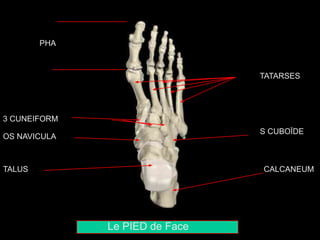

Le PIED de Face

TALUS CALCANEUM

OS NAVICULAIRE

3 CUNEIFORMES

OS CUBOÏDE

5 METATARSES

PHALANGES

Le PIED deFace TALUS CALCANEUM OS NAVICULAIRE 3 CUNEIFORMES OS CUBOÏDE 5 METATARSES PHALANGES